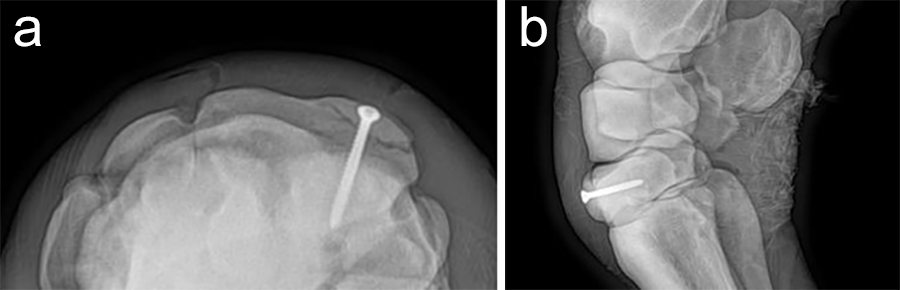

A 1.6 mm guide wire was advanced through the bone to assess the correct positioning of the targeting clamp. The guide wire is centered within the cyst. At this stage, the ideal screw length was measured on the perioperative radiographs. When using these headless cannulated compression screws, remember that the shaft thread length is approximately 40% of the screw length. Ideally, the threaded shaft of the screw is positioned on the trans-side of the cyst. The 3.2/1.6 mm insert sleeve was then removed and the bone was drilled with a cannulated 3.2 mm drill bit to the required length (Fig 8a). Considering the high-bone density at this location, the entire length of the drill hole was tapped by hand with a cannulated 4.5 mm tap through the 4.5 mm drill sleeve. Next, a 4.5 mm headless compression screw was inserted through the 4.5 mm drill sleeve and tightened by hand (Fig 8b). The stab incision was closed routinely. The horse was covered with a two-layer bandage. The total surgery time was 30 minutes.

Postoperative radiographs showed accurate screw positioning (Fig 9). The horse was box-rested for 2 weeks and hand-walked for another 6 weeks. Ridden work was resumed after 2 months. The horse remained sound in the postoperative period. Four months after surgery, the radiographic definition of the cyst margins was markedly decreased.